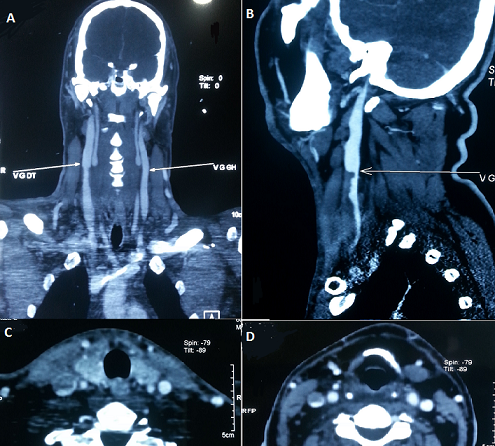

A 46-years-old patient with a 7 years history of oral and genital recurrent ulceration with ocular redness since one year. He was admitted for the management of edema of the face and the neck, the onset was progressive without fever or poor general condition. On physical examination, the patient was aware, he had no fever, heart rate at 80b / min, blood pressure= 14/7, Spo2= 100%. There was no murmur on auscultation of the cervical vessels, and no neurologic deficit. Computed Tomography angiography was performed and revealed an almost complete thrombosis of the right internal jugular vein along 9 cm. the patient received curative dose anticoagulant therapy with good evolution. Behçet's disease is a multisystem disease characterized by a bipolar ulceration, skin lesions, and systemic vasculitis. The prevalence of vascular disease is about 25% and it alone represents the leading cause of death in this condition. Jugular thrombosis is an unusual event. Recent data from the literature support the beneficial effect of anticoagulation associated with corticosteroids and immunosuppressive therapy in its management.